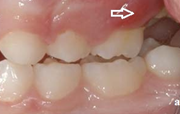

Ülemise hambakaare kitsenemine ehk tagumiste hammaste risthambumus.